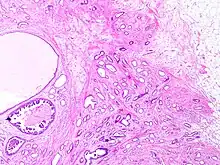

Tubular carcinomas are generally around 1 cm. or smaller, and are made up of tubules. They are usually low-grade.[2] Elastosis has been noted as common but is not present in all cases.[11]

- 1 2 Image by Mikael Häggström, MD. Reference for typical features: Pragya Virendrakumar Jain, M.D., Julie M. Jorns, M.D. "Breast - Other invasive carcinoma subtypes, WHO classified - Tubular". Pathology Outlines.

- 1 2 Stavros, A. Thomas (2004). Rapp, Cynthia L.; Parker, Steve H. (eds.). Breast Ultrasound. Lippincott Williams & Wilkins. pp. 647–649. ISBN 978-0-397-51624-7. OCLC 1065689596. p. 649:

A highly differentiated invasive carcinoma that forms well-defined tubules (containing epithelium, but no myoepithelium) and that have abundant desmoplastic fibrous stromal reaction between the tubules.